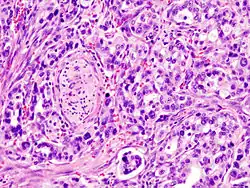

Rak gruczołowy przewodowy (barwienie H+E)

Rak gruczołowy przewodowy

Rak gruczołowy przewodowy stanowi 80–85% wszystkich przypadków nowotworów złośliwych trzustki. Najczęściej jest zlokalizowany w głowie trzustki, rzadziej w trzonie i ogonie. Makroskopowo są to twarde, słabo odgraniczone guzy, na przekroju koloru żółtego lub białego. Obszary martwicy lub krwotoków nie są częste, mogą być widoczne mikrotorbiele[111].

Gruczolakoraki przewodowe są to zwykle nowotwory dobrze lub średnio zróżnicowane (niski i pośredni stopień złośliwości histologicznej). Mikroskopowo charakteryzują się występowaniem dość dobrze rozwiniętych struktur gruczołowych, przypominających struktury prawidłowego utkania trzustki. W obrębie guza mogą występować różnice zróżnicowania, ale rzadko są obecne ogniska raka o niskim zróżnicowaniu w obrębie raka o wysokim zróżnicowaniu[113].

W wysoko zróżnicowanym raku występują duże struktury przypominające przewody w połączeniu ze średniej wielkości nowotworowymi gruczołami. Typowo występuje cewkowy lub sitowy wzór gruczołów. Gruczoły nowotworowe są niecałkowicie uformowane lub przerwane. Zrąb jest desmoplastyczny, a duża zawartość włókien stanowi przyczynę twardej konsystencji. Pomiędzy nowotworowymi gruczołami mogą występować wyspy prawidłowego utkania tkanki trzustki, zawierające nienowotworowe, prawidłowe gruczoły, pęcherzyki trzustkowe i wysepki trzustkowe. Możliwe jest tak wysokie zróżnicowanie nowotworu, że pod mikroskopem bardzo trudno rozróżnić go od prawidłowej tkanki. Atypowe komórki są walcowatego kształtu, zwykle większe od prawidłowych komórek; zawierają eozynofilną lub bladą cytoplazmę, zawierają duże okrągłe lub owalne jądro komórkowe o zróżnicowanej wielkości. Zwykle wytwarzają mucyny. Mimo występowania jądra komórkowego przy podstawie komórki obserwuje się utratę polaryzacji komórki. Aktywność mitotyczna jest niska[113].

W umiarkowanie zróżnicowanym gruczolakoraku przewodowym obserwuje się mieszaninę średniej wielkości struktur przypominających przewody lub cewki osadzone w desmoplastycznym zrębie. Częste jest niecałkowite uformowanie gruczołów. Komórki wykazują większe zróżnicowanie wielkości jądra komórkowego i są widoczne jąderka w porównaniu do raka wysoko zróżnicowanego. Często widoczne są figury mitotyczne. Cytoplazma komórek jest eozynofilna lub blada, produkcja mucyn jest mniejsza niż w gruczolakoraku wysoko zróżnicowanym. Mogą występować ogniska niskiego lub nieregularnego zróżnicowania, szczególnie w obrębie brzegów nowotworu naciekającego tkanki okołotrzustkowe[113].

Gruczolakoraki nisko zróżnicowane są rzadkie. Są zbudowane z licznych, ściśle upakowanych, nieregularnych gruczołów, ale mogą również występować jako lite guzy zbudowane z warstw lub gniazd atypowych komórek. Komórki mogą być płaskie lub wrzecionowate, wykazują znaczny pleomorfizm i nie produkują mucyn. Występuje znaczna aktywność mitotyczna. Mogą występować ogniska anaplastyczne, które z definicji nowotworu nigdy nie przekraczają 20% guza. Może być obecny naciek z komórek zapalnych. W obrębie brzegu nowotworu okoliczne tkanki są nacieczone przez osobne gniazda komórek nowotworowych[113].